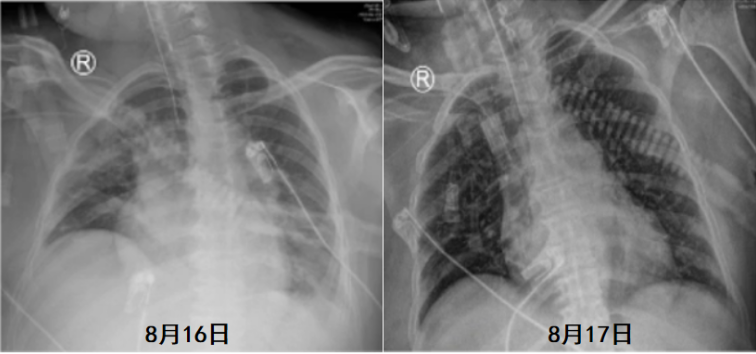

经抗感染治疗后患者仍反复发热,最高体温39.0°C。患者插管当天及插管后6天的血气分析和炎症指标如表1和表2所示,氧合较前好转,炎症指标下降。胸部X线片未见明显进展(图2)。

经过上述治疗,患者炎症指标有所下降(表5),胸部X线片较前好转(图7)。

8月19日复查血气分析(呼吸机辅助呼吸,SPONT模式,PSV 18 cmH2O,PEEP 8 cmH2O,氧浓度35%):pH 7.520,PaCO2 56.0 mmHg,PaO2 144.0 mmHg,SaO2 99%。SBT通过,复查支气管镜见气道内少许分泌物,黏膜光滑无肿胀,于8月19日脱机拔管,序贯无创呼吸机辅助呼吸。气管导管尖端培养、灌洗液培养(8月19日送检)均为肺炎克雷伯杆菌;血培养(8月16日送检)为白色念珠菌。血NGS回报金黄色葡萄球菌(序列数3),覆盖度0.01%。继续延用替加环素+多黏菌素B+卡泊芬净的治疗方案。患者8月19日拔管后仍出现反复发热,考虑仍与感染有关。然而,从8月21日胸部X线片可见肺部病变有所好转(图8)。8月22日胸部CT可见两侧胸腔积液明显吸收,双肺实变、渗出灶较前明显好转(图9)。考虑患者发热的原因可能并非肺部感染。8月23日查体见患者背部、腹股沟区、左下肢点片状红疹。考虑可能为药物热所致,遂停用多黏菌素B、替加环素,改为哌拉西林他唑巴坦4.5 g ivgtt q8h抗感染治疗,继续卡泊芬净抗真菌治疗。调整治疗方案后患者最高体温下降,但仍有发热。为了排查感染问题,8月26日拔除PICC管,之后2~3天,患者体温逐渐恢复正常。因此考虑患者可能合并血流感染。之后患者一般情况好转,8月27日复查胸部X线片提示病情进一步好转(图10)。8月29日转入普通病房,后一直未再发热,9月13日出院。